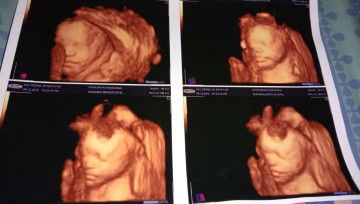

Rambut sedikit

Bun recom shampo ato hair lotion yg bikin rambut bayi lebat donk.. Umur 1bulan rambutx msh tipis sekali.